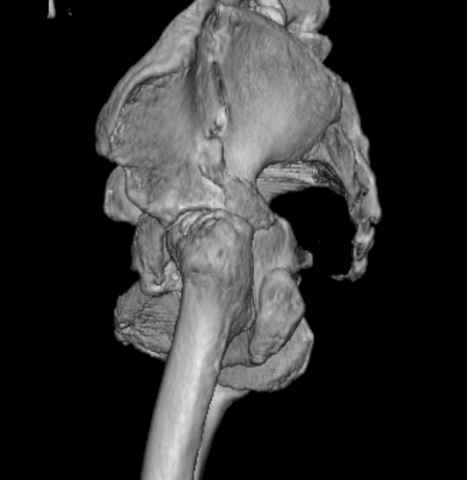

Уважаемые коллеги, возник вопрос по лечению нашей пациентки 60 лет. Около года назад множественная травма: в том числе Т-образный перелом вертлужной впадины. На сегодняшний день сращение отломков имеется на ограниченных участках, имеется дефект задней колонны вертлужной впадины. Движения неплохие, ходит с костылями, приступая на ногу. По мнению эдопротезистов при установке антипротрузионного кольца или октопуса не хватит костного материала и необходимо перед протезированием выполнить реконструкцию впадины, иначе чашка протеза неминуемо выпадет.Просьбы поделиться положительным и отрицательным опытом протезирования в подобных случаях.Возможно ли обойтись без реконструкции?Или лучше с ней?С уважением РАВ.